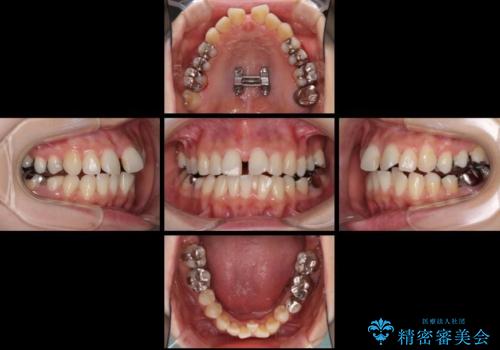

上顎骨拡大を併用したインビザライン矯正

- 上下のデコボコと奥歯の咬みにくさを気にして来院された患者様です。

上顎骨の幅が下顎骨よりも小さいので、拡大装置により骨幅を広げて上下関係を改善し、その後インビザラインにて歯並びを整えることとしました。

上下の骨幅を改善したことで、スムーズに歯列矯正を行うことができました。

矯正治療中に近医で銀歯を外す治療を開始したため、治療後に奥歯の咬み合わせが不十分ですが(こちらは近医での治療により改善するとのこと)、歯列と咬み合わせが改善され、患者様には大変満足していただきました。